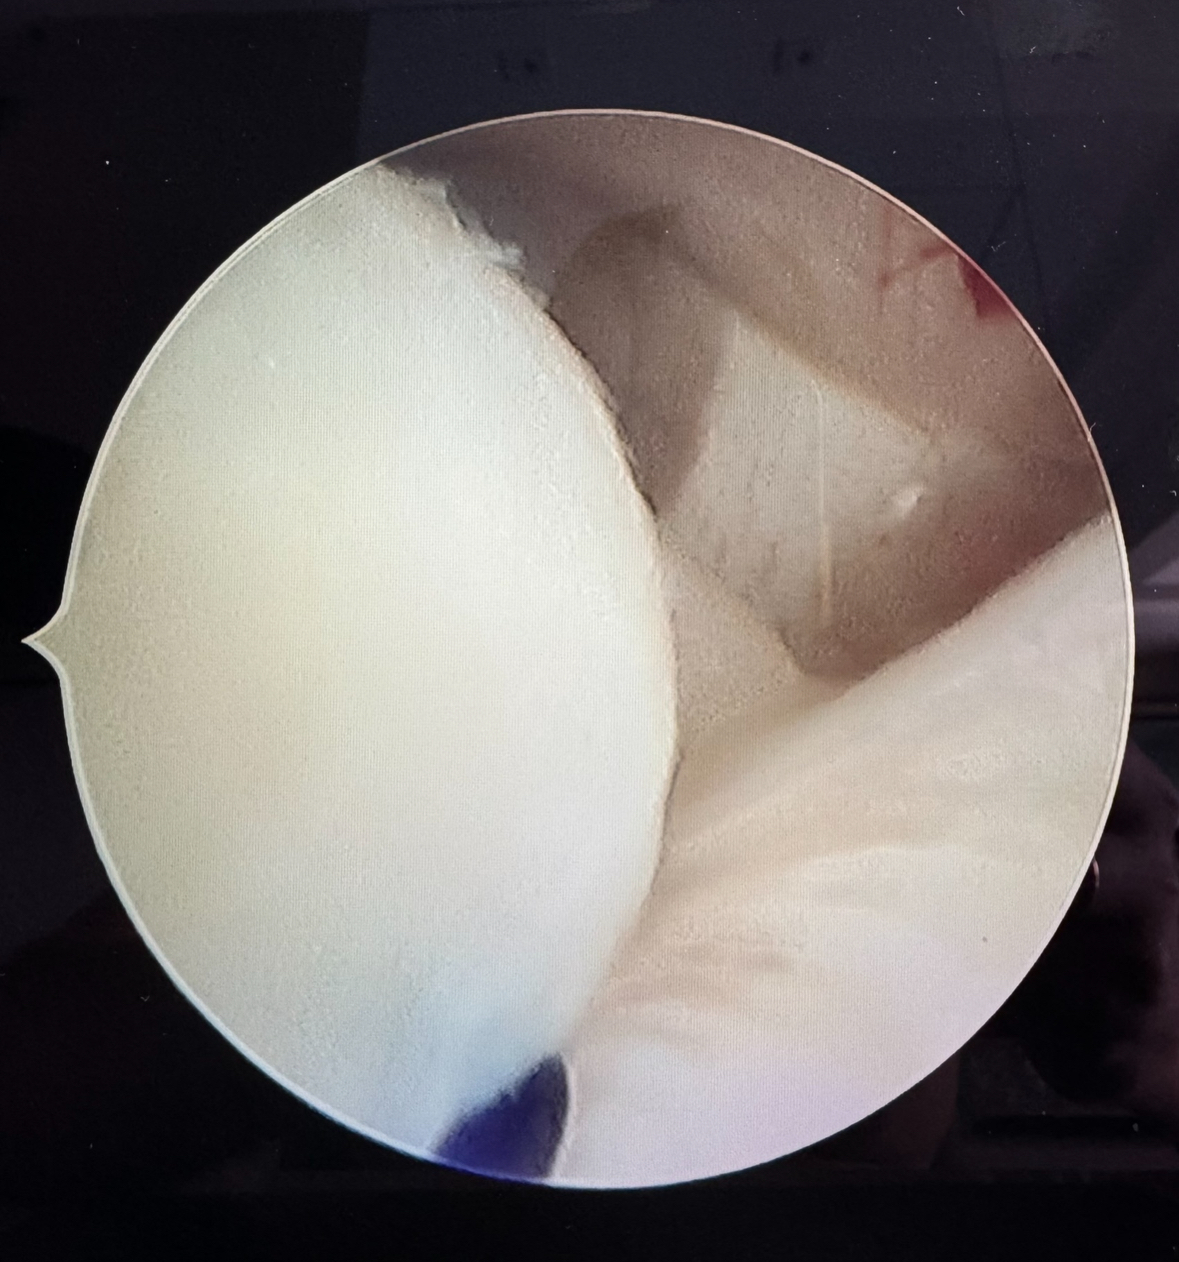

The technique demonstrated a reduction in operative time due to the lack of need for a fourth working portal, making the procedure simpler and faster. There was successful repositioning and stabilization of the TMJ disc, as demonstrated by arthroscopic imaging (Figure 3) and post-surgical magnetic resonance imaging. Patients reported improvement in TMJ pain and increased mouth opening during our postoperative follow-up.

Figure 2: use of the catheter itself with the thread for exit through the external auditory canal approach .jpg) Figure 3: disc in normal position after discopexy

Figure 3: disc in normal position after discopexy